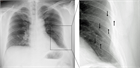

1. 単純X線での診断は困難なことも多く、肋骨条件や斜位像の追加が有用(推奨度2)